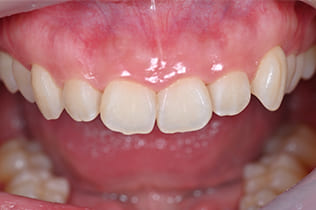

Case01

-

- 原因

- ガミースマイル

- 治療回数

- 1回

- 治療期間

- 術後治癒も含めて約1か月

- 治療内容

- ガミースマイル改善治療

- 治療費用

- 121,000円

(1ブロックあたり、6前歯部分)

笑った時に歯茎が見えてしまうガミースマイルを改善したいとのことでご来院された患者様です。術後も大変満足していただきました。